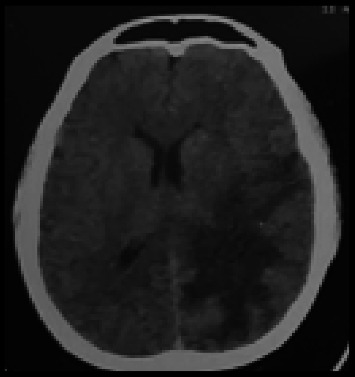

血吸虫病是由血吸虫属寄生虫感染引起的被忽视的热带病之一。血吸虫病累及大脑是感染的一种特别严重的表现。准确诊断和适当治疗脑血吸虫病至关重要,特别是在我们位于印度尼西亚偏远地区的卫生保健设施中,那里的可用资源非常有限。我们报告了一位31岁的女性患者,主诉强直阵挛性惊厥。在癫痫发作前,患者报告头痛6个月。患者对社会生活的记忆显示,她在一个种植园工作了15年;该种植园是蜗牛的自然栖息地,蜗牛是血吸虫的中间宿主。由于该地区诊断仪器的限制,未进行血清学检查。根据活检、粪便检查和CT扫描结果证实脑血吸虫病的诊断。患者入院时使用类固醇和吡喹酮联合用药,单次剂量为60mg /kg。她在14天后出院,总体健康状况令人满意。后续的CT扫描显示改善,证实了患者的临床恢复。本报告强调了与脑血吸虫病相关的诊断障碍,特别是在印度尼西亚的偏远地区和资源有限的环境中。尽管缺乏血清学检测,但通过放射成像、粪便显微镜检查和脑组织活检(组织病理学分析)成功地建立了明确的诊断,发现血吸虫卵周围有肉芽肿性炎症。患者表现为脑部占位性病变和神经系统症状,但未累及肝脏,使诊断不太直截了当。本病例说明了在流行地区出现脑病变的患者中,将脑血吸虫病作为鉴别诊断的重要性。当没有其他诊断工具(血清学检测)时,基于与放射成像、粪便显微镜检查和脑组织活检(组织病理学分析)相关的详细社会职业史来诊断脑血吸虫病是必不可少的。

Schistosomiasis is one of the neglected tropical diseases caused by parasitic worm infections of the genus Schistosoma. Involvement of the brain in schistosomiasis represents a particularly severe manifestation of the infection. Accurate diagnosis and appropriate treatment of cerebral schistosomiasis are essential, especially in our healthcare facility located in a remote area of Indonesia, where available resources are highly limited. We reported a 31-year-old female patient complaining of tonic-clonic convulsions. Before experiencing seizures, the patient reported experiencing headaches for 6 months. The patient's anamnesis regarding her social life revealed that she has been employed on a plantation for 15 years; the plantation serves as a natural habitat for snails, intermediate hosts for Schistosoma sp. Serological examinations were not performed due to the constraints of diagnostic instruments in the region. Cerebral schistosomiasis diagnosis was verified based on biopsy, stool examination, and CT scan results. She was admitted with a combination of steroids and praziquantel at a dosage of 60 mg/kg single dose. She was released after 14 days in satisfactory overall health. The follow-up CT scan revealed improvement, corroborated by the patient's clinical recovery. This report emphasizes the diagnostic obstacles associated with cerebral schistosomiasis, particularly in remote regions and resource-limited settings in Indonesia. Despite the absence of serological testing, a definitive diagnosis was successfully established through radiological imaging, stool microscopic examination, and brain tissue biopsy (histopathological analysis) which revealed Schistosoma eggs surrounded by granulomatous inflammation. The patient presented with space-occupying brain lesions and neurological symptoms, but without hepatic involvement, making the diagnosis less straightforward. This case illustrates the significance of recognizing cerebral schistosomiasis as a differential diagnosis in patients presenting cerebral lesions in endemic locations. Diagnosis of cerebral schistosomiasis based on a detailed social occupational history correlated with radiological imaging, stool microscopic examination, and brain tissue biopsy (histopathological analysis) is essential when other diagnostic tools (serological testing) are unavailable.